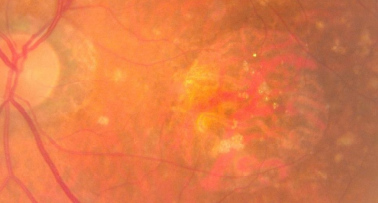

DMAE avanzada neovascular

| DMAE avanzada húmeda | NVC activa: exudación, hemorragias, desprendimiento de EPR o neurosensorial. Progresión rápida sin tratamiento | N/A | Variable | URGENTE |

- Detección de signos de neovascularización (exudados, hemorragias)

- Evaluación estructural de drusas, EPR, capas retinianas externas

- Detección de fluido intra/subretiniano (signo de actividad neovascular)